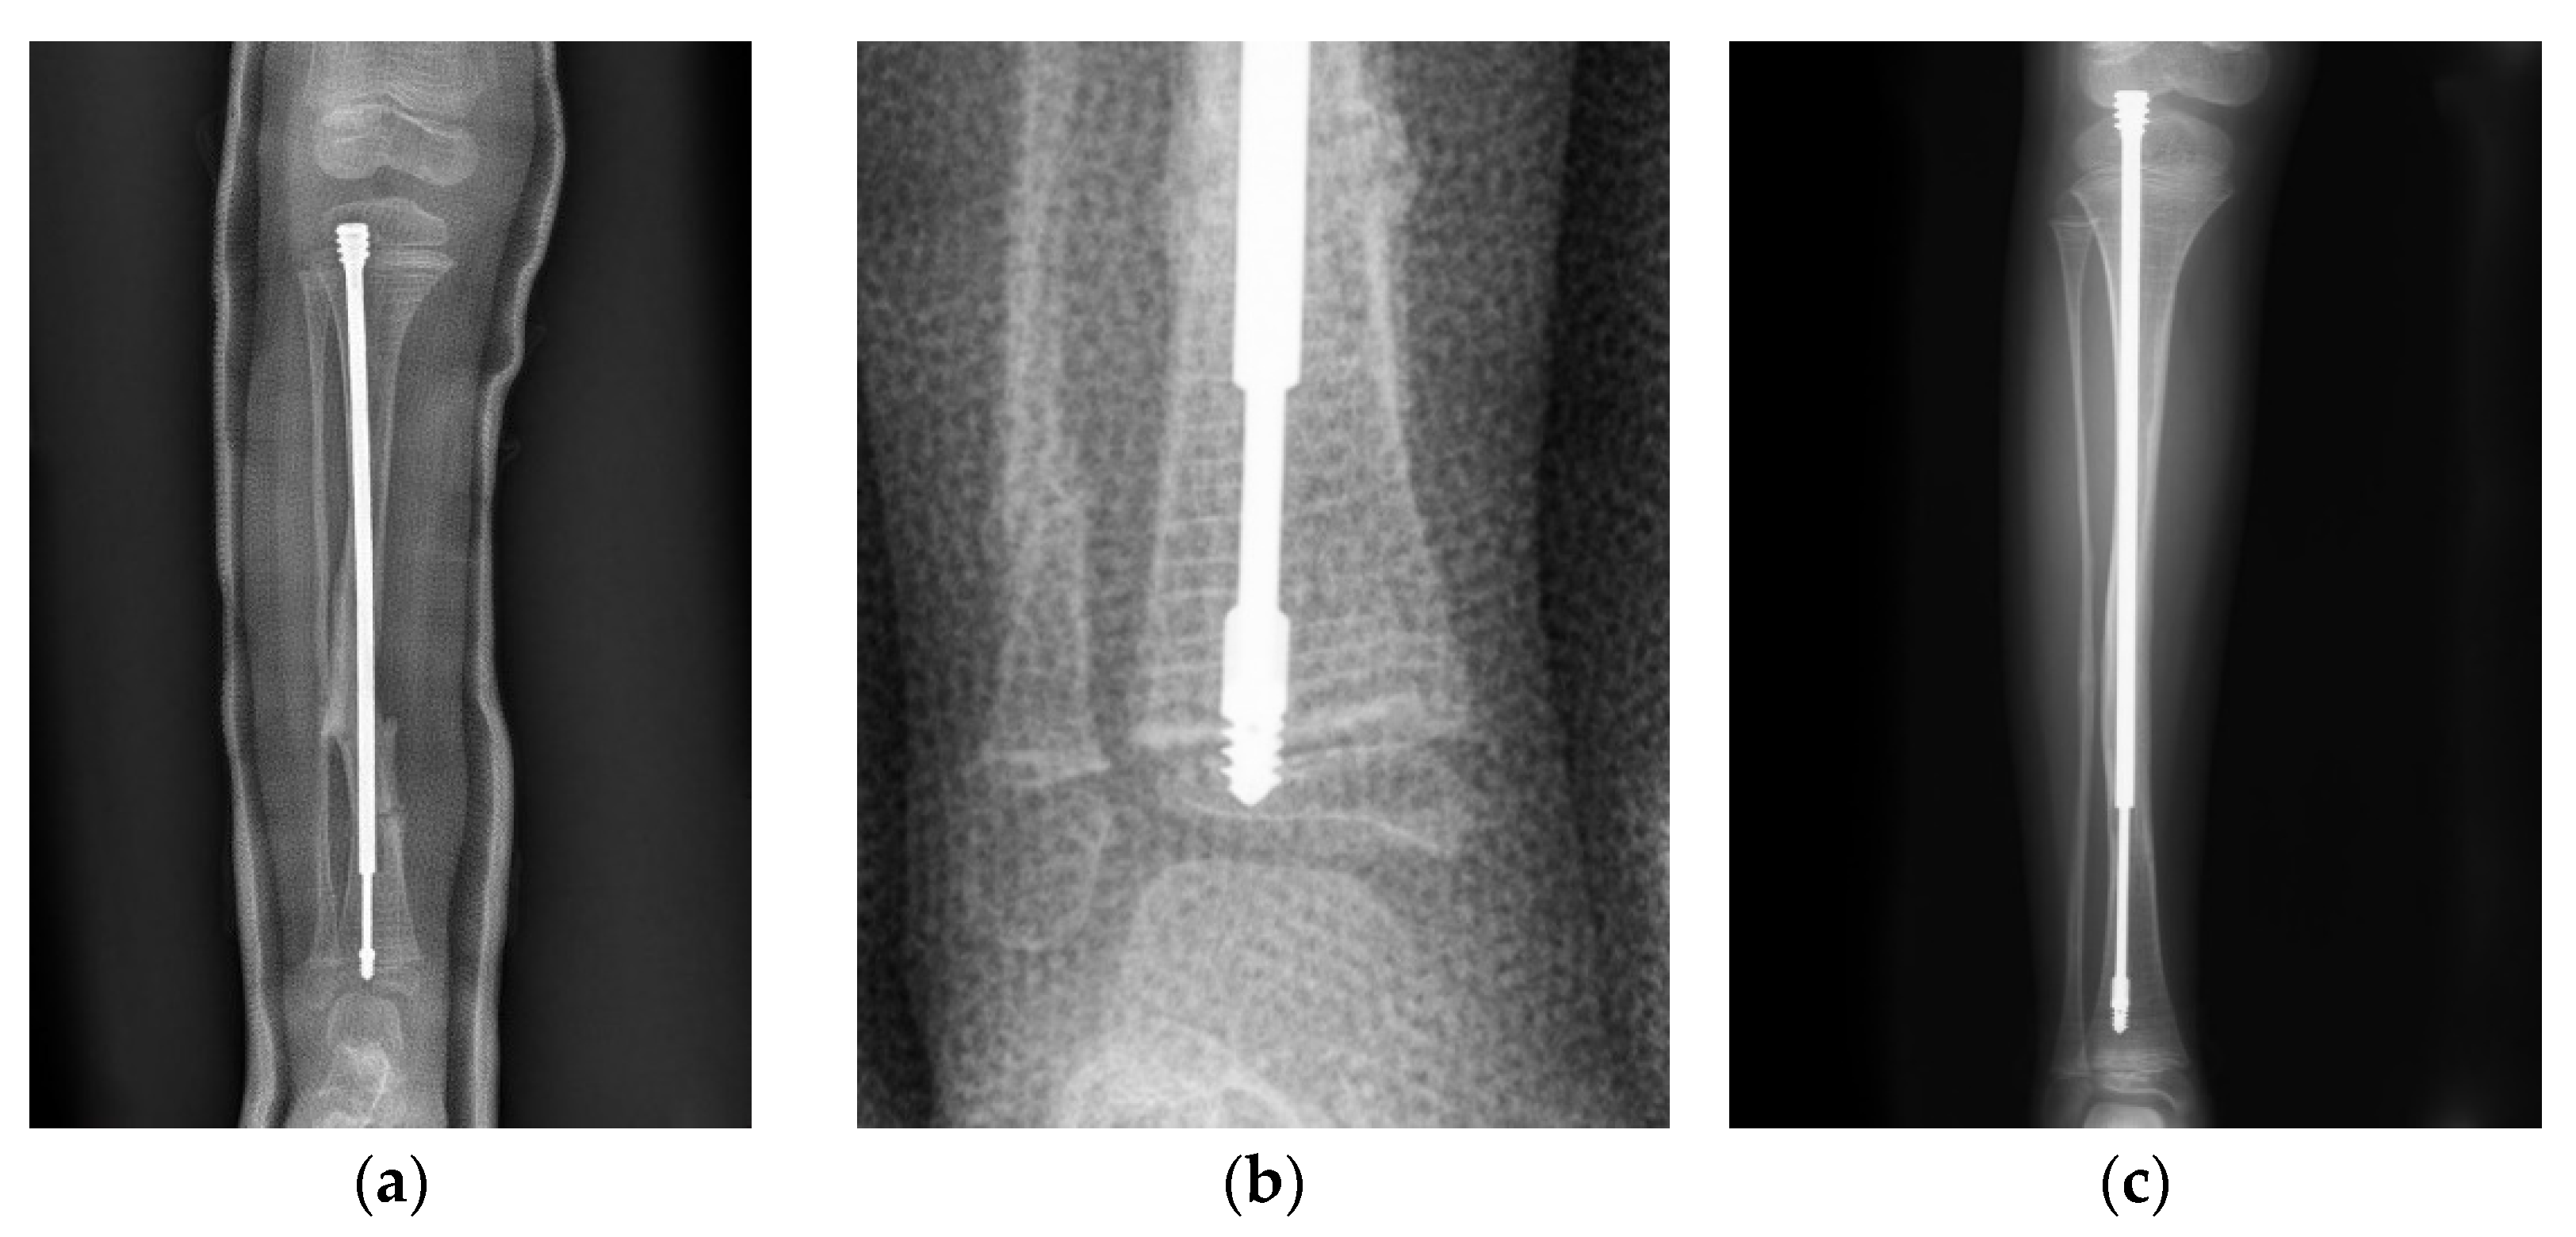

In a case of a 4-year-old female with type III OI (Figure 1), the position of the male component was quite central in the distal epiphysis on both anteroposterior and lateral views. However, there was insufficient purchase of the male component tip (Figure 1a). If the threads end just around the physis instead of beyond it (Figure 1b), distal dislodgement would occur along with growth of the limb (Figure 1c). However, this raises the question of how to ensure sufficient depth of the male implant intraoperatively. We suggest the following steps: First, center the male component at the center of the distal epiphysis as far as possible so that the thickest epiphysis is purchased. The thread of the male component needs to be fully submerged into the epiphysis, and the flange of the nail must exceed the physis, or at least stop at the level of the physis. If the distal epiphysis of the tibia is small, the tip of the nail may reach the subchondral area to ensure that the whole thread goes through the physis (Figure 2). Since the distal epiphysis of the femur is larger than the distal epiphysis of the tibia, there is a relatively lower risk of distal dislodgement in the femur (tibia 4, femur 1 in our series) due to sufficient distal purchase.

Migration of the male component is common in the tibia due to an almost empty epiphysis [18,19]. For the male component, short thread screws are designed to anchor the epiphysis and resist a pulling out force due to growth [15]. A keyhole over the screw thread adds strength to the distal fixation. The fixation-wire with a diameter ranging from 0.7 mm to 1.1 mm for the corresponding nail can increase more anchorage [11], however, it was relatively difficult to facilitate targeting the keyhole with such a small fixation-wire. In addition, non-threaded (LON) male components with peg fixation and larger keyhole (1.5 mm) [11] are not currently available in Taiwan. Thus, we could only follow the principles mentioned above to ensure maximal distal fixation.

Figure 2. The first principle to decrease the revision rate is to ensure sufficient purchase. The thread of the male component needs to be fully submerged into the epiphysis, and the flange (*) of the nail must exceed the physis or at least stop at the level of the physis. If the distal epiphysis of the tibia is small, the tip of the nail may reach the subchondral area (arrow) to ensure that the whole thread goes through the physis.